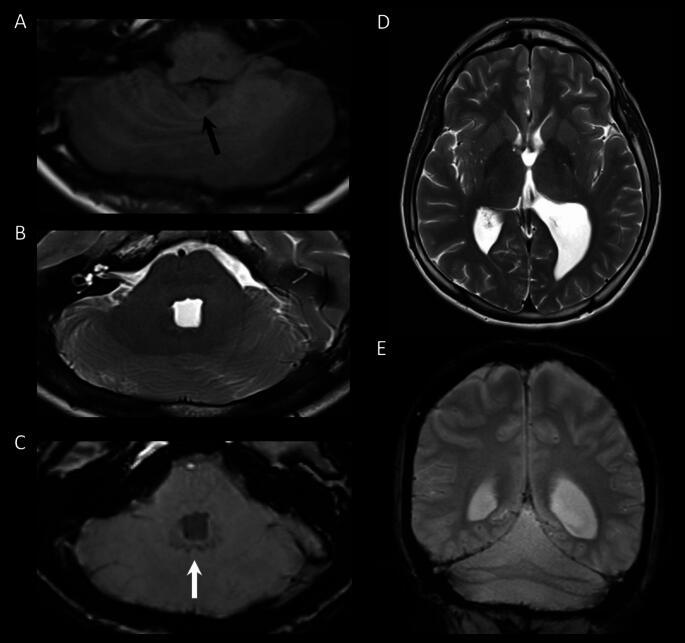

Rhombencephalosynapsis (RES) is a hindbrain malformation characterized by a missing cerebellar vermis with apposition or fusion of the cerebellar hemispheres. The present clinical case report provides a comprehensive, longitudinal overview of cognitive and affective manifestations in a 22-year-old patient with RES. The patient shows clinical signs of emotional reactivity and dysregulation, impulsivity, and impairments in executive functioning since early childhood. These features fit the constellation of neuropsychiatric symptoms observed in patients with congenital and acquired abnormalities of the posterior vermis. It is proposed that patients with RES may show affective and cognitive difficulties which increase their vulnerability to psychological stress and risk of developing mental health issues.

菱形脑结合(RES)是一种后脑畸形,其特征是小脑蚓部缺失,小脑半球对位或融合。本临床病例报告提供了一位 22 岁 RES 患者认知和情感表现的全面、纵向概述。该患者自幼儿期起就表现出情绪反应和失调、冲动以及执行功能障碍的临床症状。这些特征符合后天性和获得性后小脑蚓部异常患者所观察到的神经精神症状组合。因此,RES 患者可能表现出情感和认知困难,这增加了他们对心理压力的脆弱性和出现心理健康问题的风险。